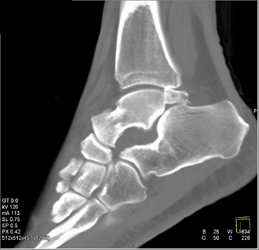

Myeloma